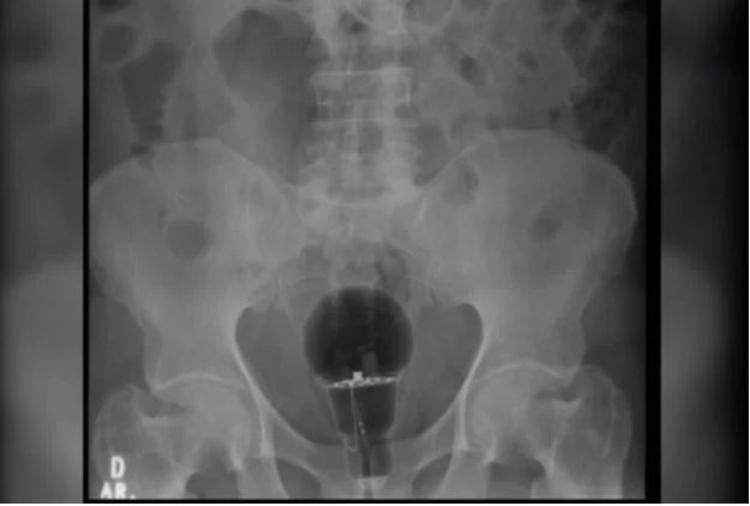

Um colombiano de 53 anos precisou passar por cirurgia após ter inserido uma lâmpada em seu ânus. O caso foi divulgado pelo médico Julian Pylor, o gastroenterologista que fez o atendimento do homem, em março deste ano, em um hospital da Colômbia, que não teve o nome divulgado.

O médico disse que o paciente chegou com dores intensas e afirmou não saber do que se tratava, no entanto, exames de imagens mostraram que ele estava com uma lâmpada no reto.

Devido ao fato da lâmpada ter sido feira de plástico, foi possível succionar o objeto, sem risco que ela se quebrasse.